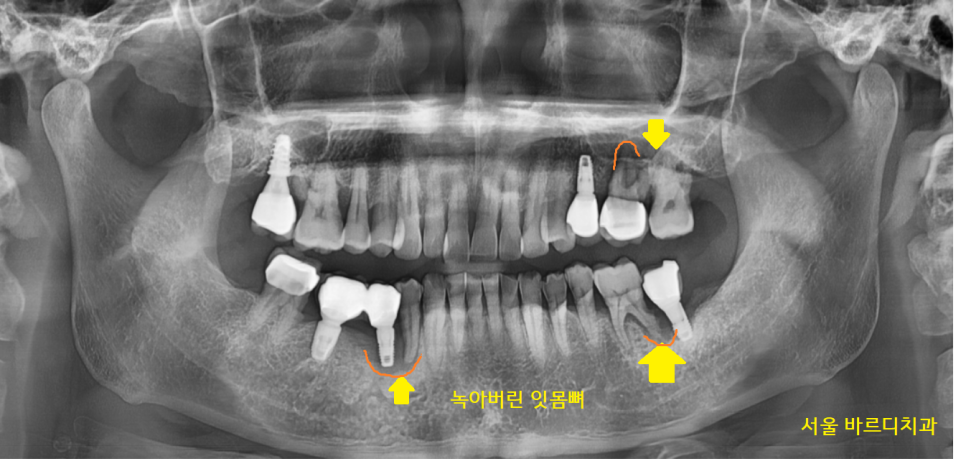

고덕동 치과 뼈이식이 필요한 환자분

케이스를 보실까요?

x-ray 상에서 잇몸 뼈가 녹은 경우에는

주변보다 까맣게 표시되는데요.

23.11.14

웅덩이가 진 것처럼 경계가 보이기도합니다.